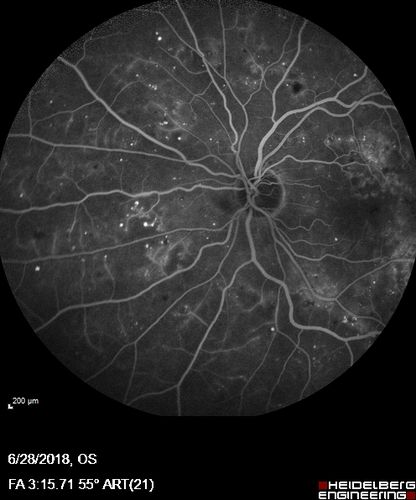

Diabetic Macular Edema with Exudates

Patient did not want injection therapy and did well with laser